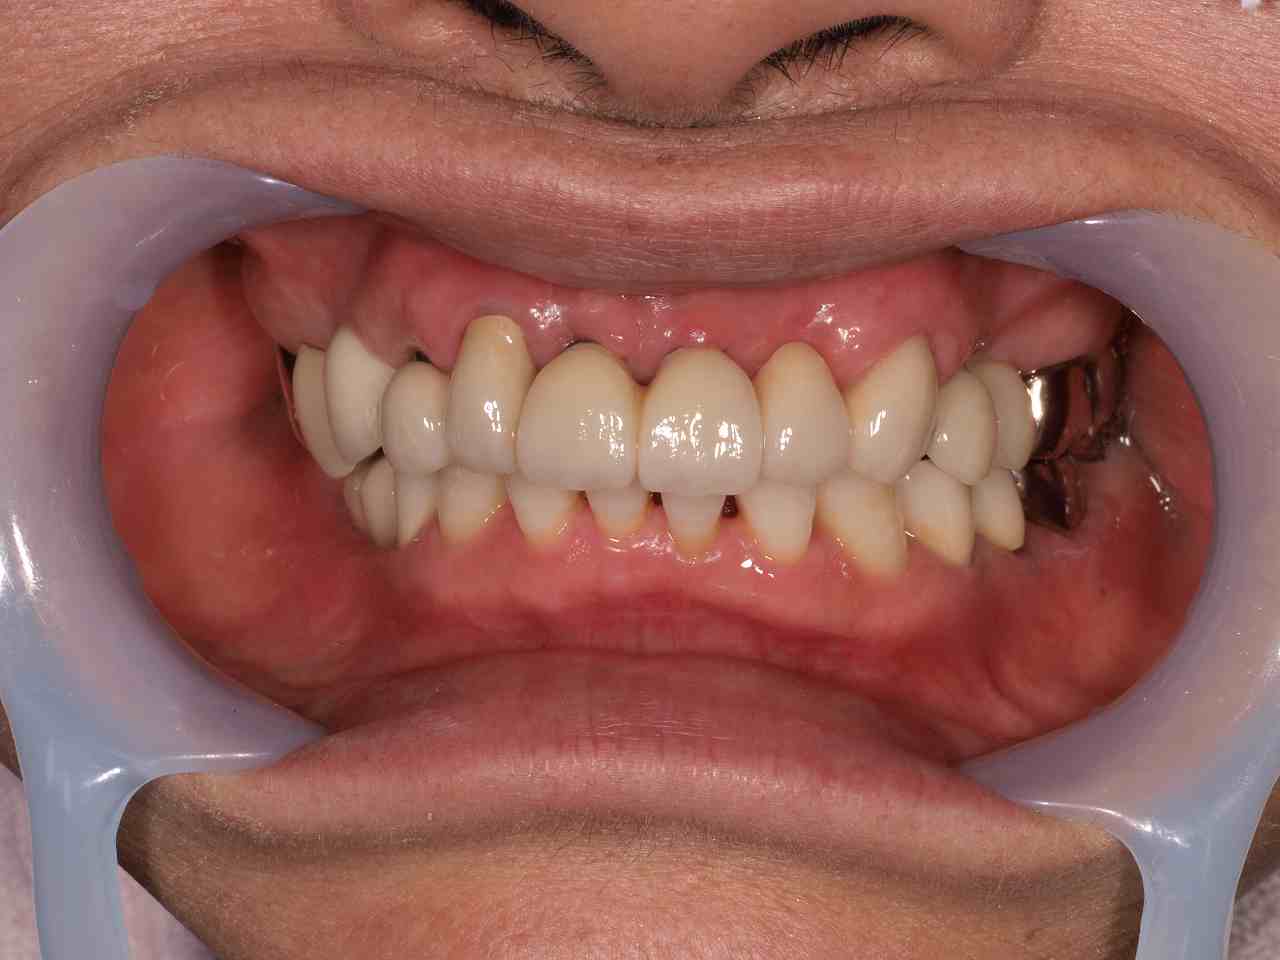

印象からのジルコニアフレームを作成しています

模型上にて

ポーセレンの築造をしていきます

大方70%のところで口腔内にて1度指摘を入れます

豊隆させたいところを見ていきます

歯軸、バランス、咬合、形態を技工士立ち合いのもと確認していきます